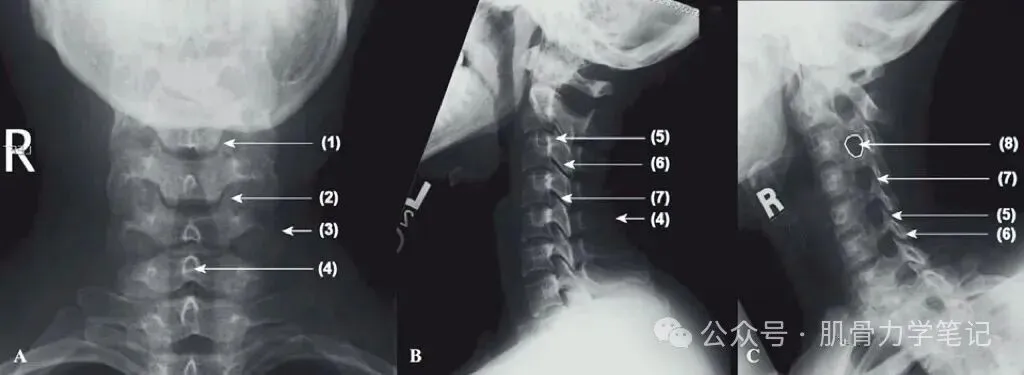

正常颈椎X线片:(A)正位, (B) 侧位, (C) 斜位

1钩椎关节, 2钩突,3侧块, 4棘突, 5上关节突,6下关节突,7关节突关节, 8椎间孔。